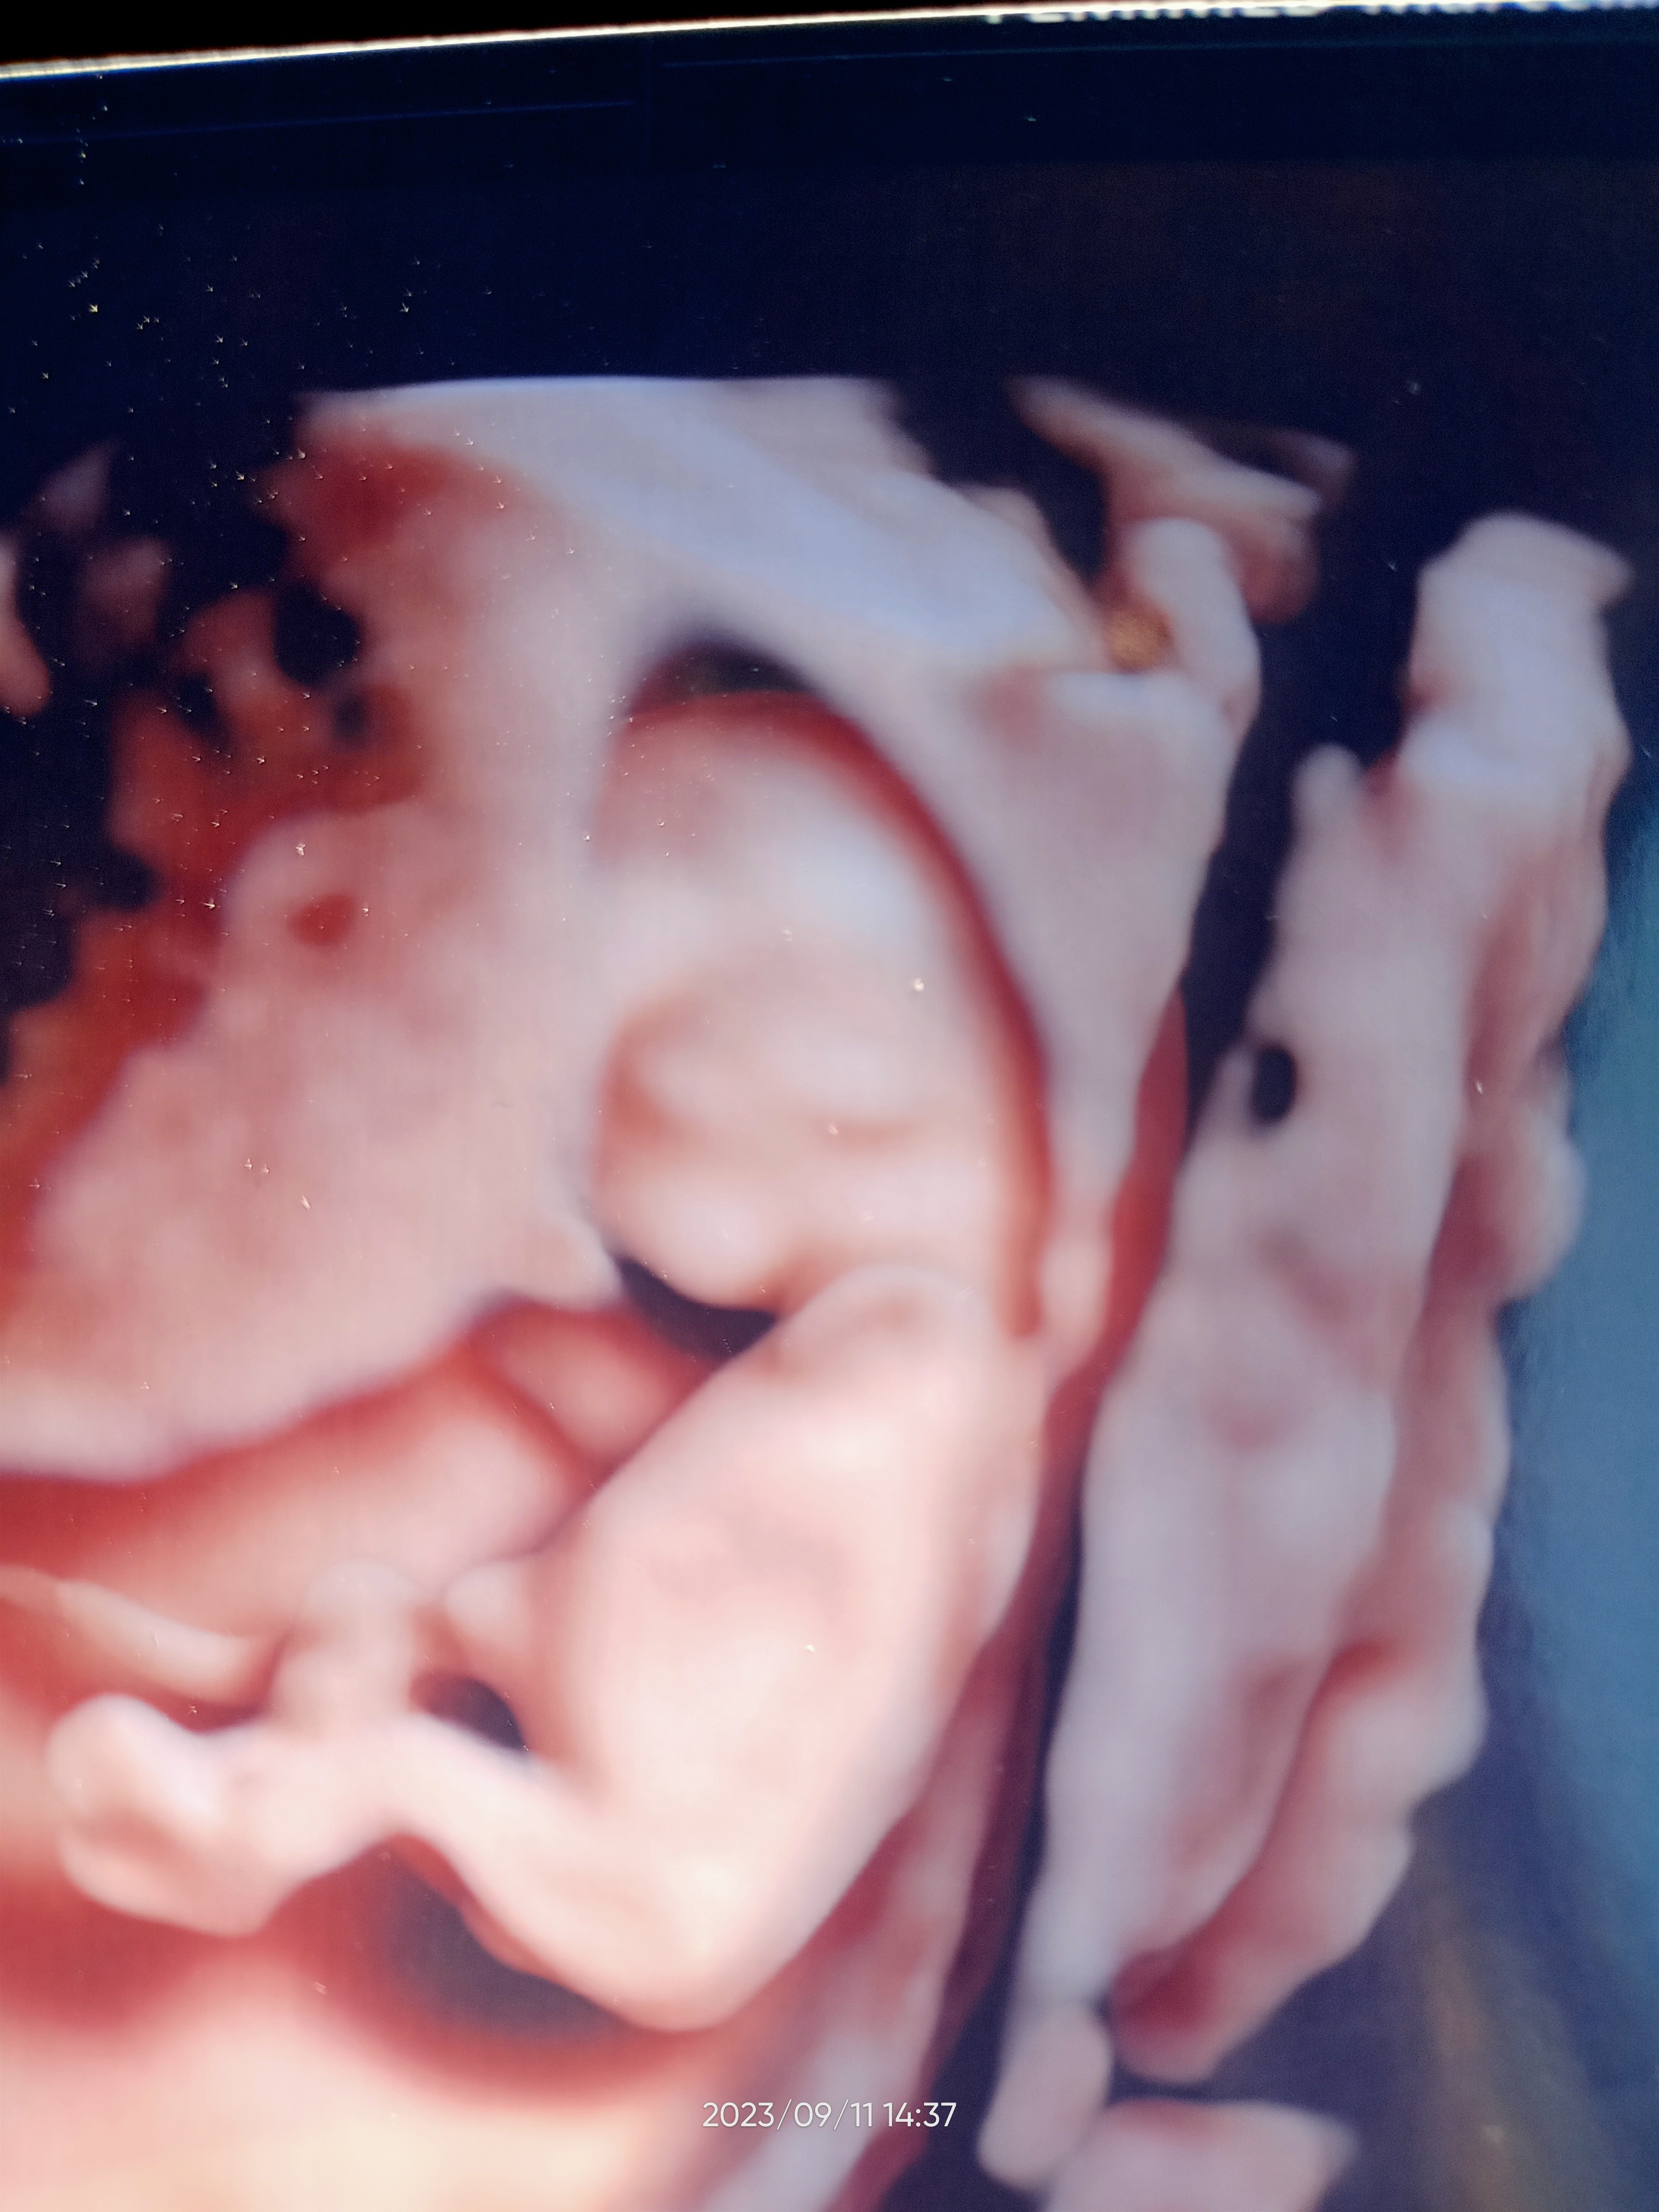

Dziewczyny jestem po. Maluch ma się dobrze. Dziś 11+3

Lekarz zrobił od razu prenatalne w cenie wizyty. Wszystko dobrze. Jak się cieszę. Na 90 % określił płeć. Ale to zdradzę wam za miesiąc. Maluch poniżej 😄

Załączniki

• IMG20230911143730.jpg

IMG20230911143730.jpg

1,5 MB · Wyświetleń: 118